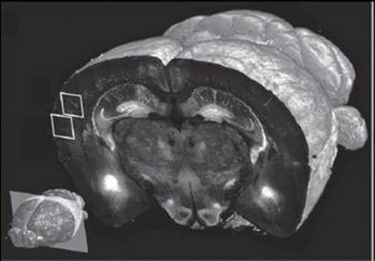

STP tomography makes possible high-throughput fluorescence imaging of whole mouse brains through robotic integration of two fundamental steps: Tissue sectioning and fluorescence imaging. In a paper describing their work, the researchers detail several experiments that highlight the sensitivity and application of the new approach—and they say it is mature enough to be used in whole-brain mapping efforts such as the Allen Mouse Brain Atlas project.

The technology can scan at resolution levels ranging from 1–2 μm to <1 μm; scans at the highest resolution level take about 24 hours, compared to one week using current methods, says associate professor Pavel Osten, who led the work. The team was able to produce full data sets, including final images, in 6.5 to 8.5 hours per brain, depending on the resolution. Each set of 260 coronal (top-to-bottom) slices was assembled by computer into 3-D renderings, which can be broadly manipulated to reveal hidden structures and features. At 10x magnification, the researchers were able to "visualize the distribution and morphology of green-fluorescent protein-labeled neurons, including their dendrites and axons," Osten notes.